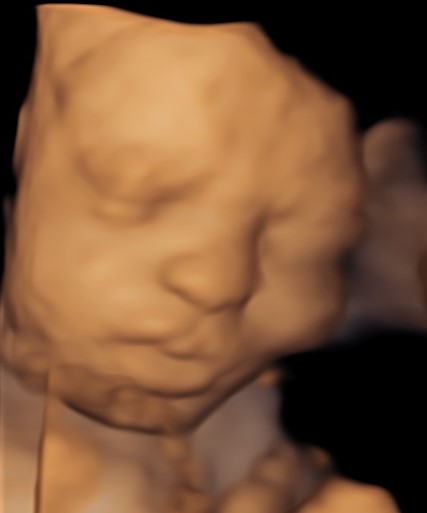

4D/5D/HD Ultrasound Gallery

Gallery